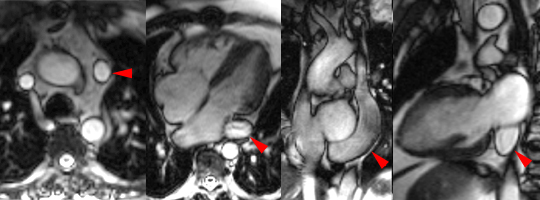

Veine cave supérieure double (flèches) chez un patient de 47 ans présentant également une sténose valvulaire pulmonaire consécutive à une ancienne réparation de tétralogie de Fallot dans l’enfance. Noter la dilatation marquée du sinus coronaire.